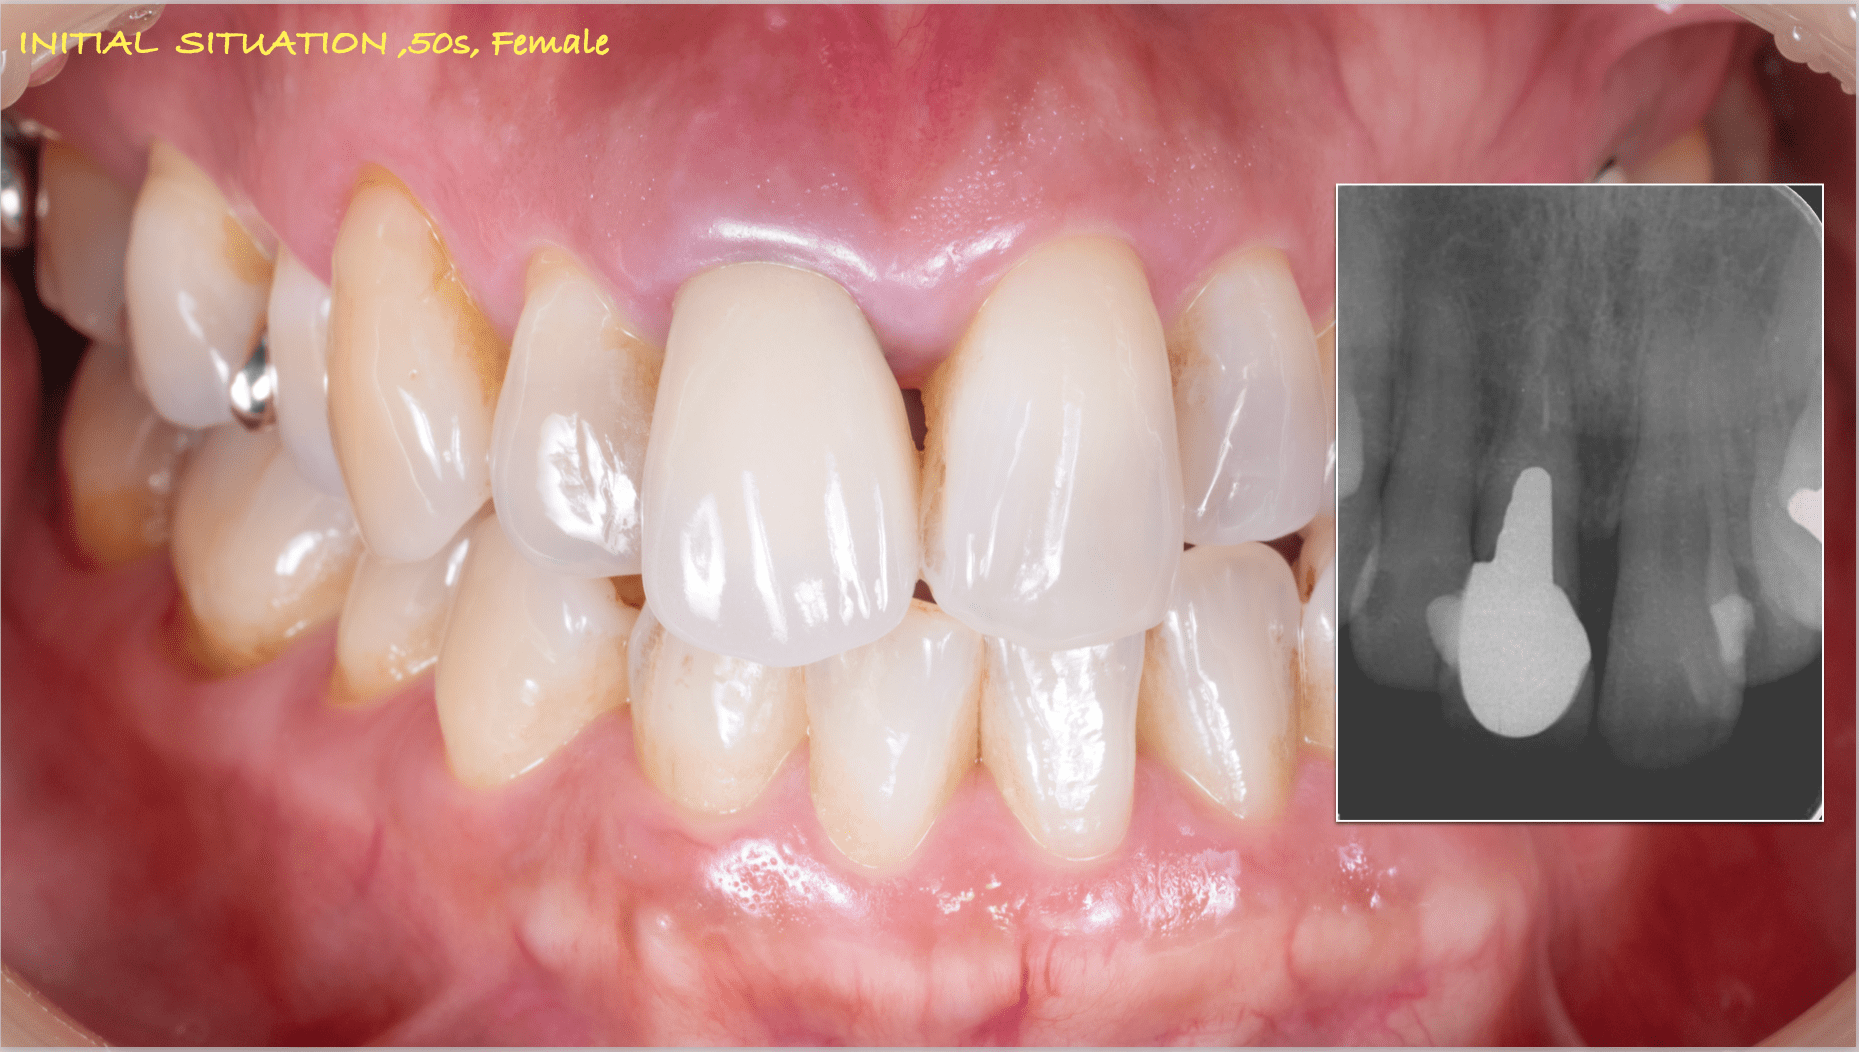

症例紹介29:インプラント治療/前歯_ソケットシール《50代女性》

年齢:50代

性別:女性

治療内容:食事中に前歯が破折し、治療を希望し来院。

術前の診査診断

術前写真

上顎:折れた歯を見ると、一部被せ物に歯が残っており保存不可能な状態。

レントゲン写真

上顎:歯には太い土台が入っており、折れて保存不可能な状態